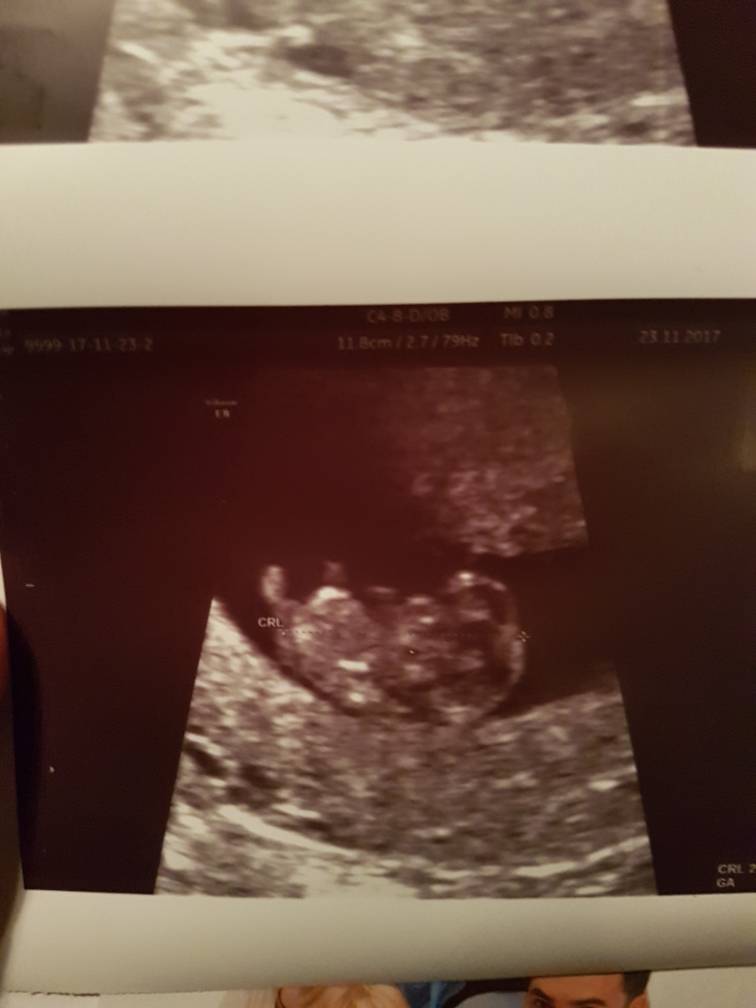

Z dzieciątkiem wszystko cudownie

2.5cm, wyniki badań książkowe, szyjka wysoko, twarda zamknięta i pięknie rozpulchniona macica.

Lekarz powiedział że wszystko super

Maleństwo widzieliśmy pierwszy raz, serducho bije jak dzwon [emoji7] machało nóżkami przez całe badanie [emoji4] coś pięknego [emoji173] wizyta za 3tyg